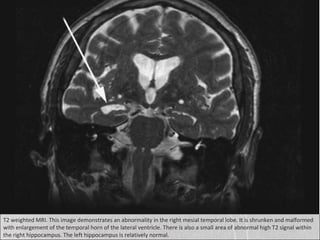

T2 weighted MRI. This image demonstrates an abnormality in the right mesial temporal lobe. It is shrunken and malformed

with enlargement of the temporal horn of the lateral ventricle. There is also a small area of abnormal high T2 signal within

the right hippocampus. The left hippocampus is relatively normal.